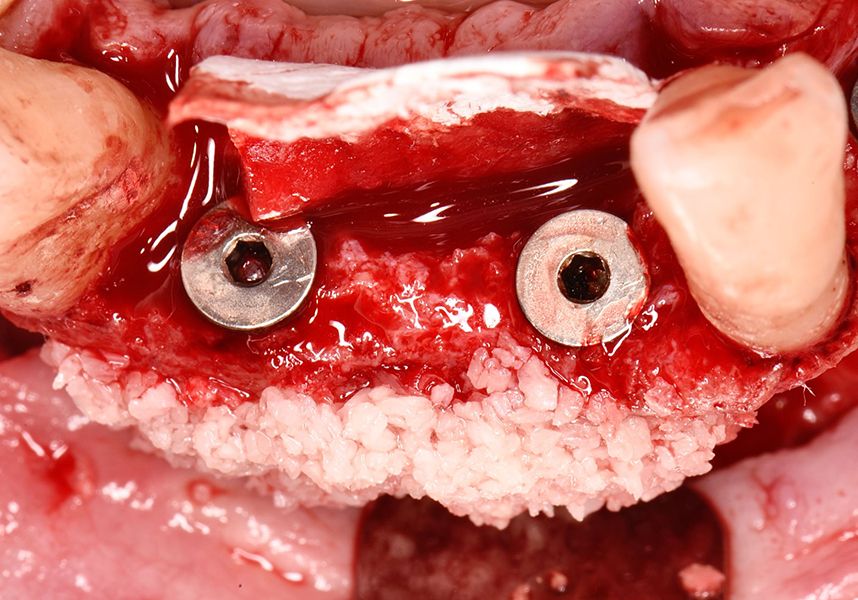

To treat the defect, bone regeneration was carried out simultaneous to the surgical process, with an autologous bone graft from the patient. In the internal part of the graft we used autologous cortical bone obtained by scraping (Safescraper) and from the biological drilling, at low revolutions and without irrigation, from the other implant beds. In the external layer of the regeneration we used a xenograft (Genoss, Osteogenos) and this was covered with a reabsorbable collagen barrier membrane (Evolution STD, Osteogenos).

The membrane was sutured with PGA reabsorbable suture to the periosteum to secure it, thus avoiding subsequent reentry to remove fixings such as tacks.

In the posterior sector three Biomimetic Ocean IC implants of 4.0x10 were inserted in positions 36, 34 and 46 with delayed load. A small regeneration was also carried out with autologous bone in the implant in position 34, where there was no exposure, but the vestibular cortical was very fine after implant insertion.